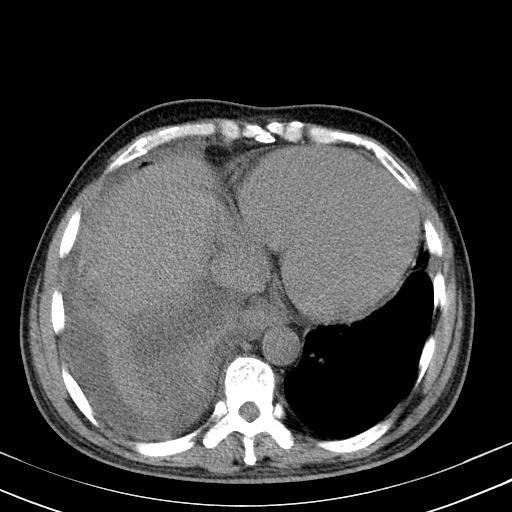

以下是引用zxl51642在2010-3-21 17:06:00的发言:[br]右下中心型肺癌并阻塞性肺炎/不张,纵膈淋巴结肿大,右侧大量胸腔积液,左侧少量胸腔积液,少量腹水。建议纤维支气管镜进一步检查。